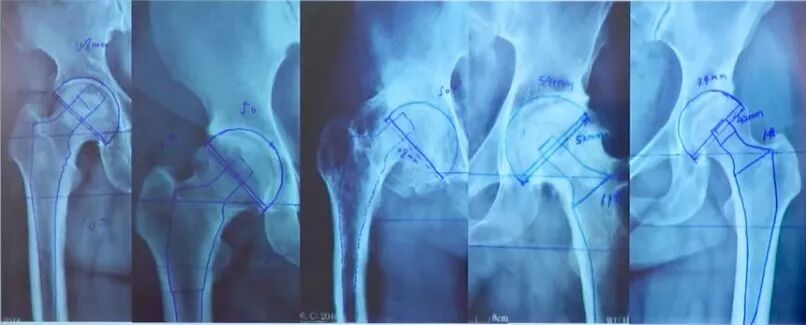

股骨模板测量:

①选择骨盆正位片与合适比例模板;

②股骨距应与模板上的股骨距部相吻合;

③对应颈长的中心应与股骨头中心相吻合;

④经过假体中心的横线应与大粗隆顶点相切;

⑤填充髓腔,注意股骨距的高度。

做完以上工作之后,我们即可以了解到:

①术前模板测量可以限定手术用假体的规格在3个以内;

②术前发现不常见的解剖异常,节省手术时间,减少透视次数。